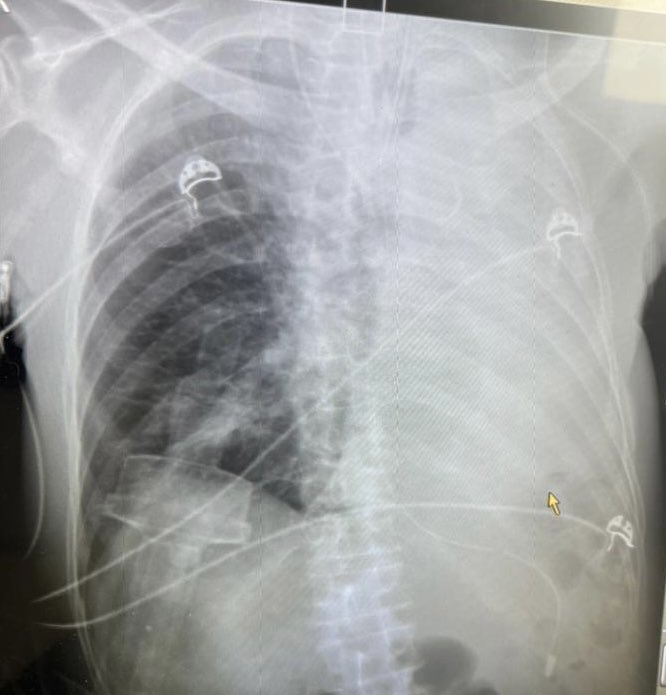

Skeletal muscle adaptations and post-exertional malaise #PEM #PESE in #LongCOVID @RobWust

cell.com/trends/endocri…